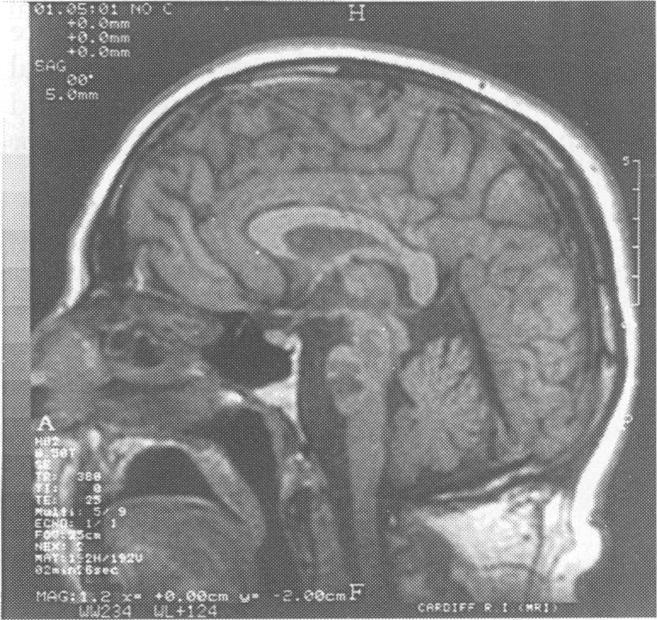

Mills' syndrome: ascending (or descending) progressive hemiplegia: a hemiplegic form of primary lateral sclerosis?

J Neurol Neurosurg Psychiatry. 1994 Oct;57(10):1280-1. doi: 10.1136/jnnp.57.10.1280.